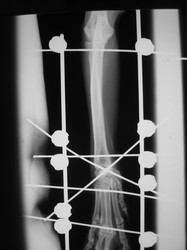

PRÁCTICAS CURSO DE FIJACIÓN EXTERNA PERFECCIONAMIENTO.

Artrodesis carpo.